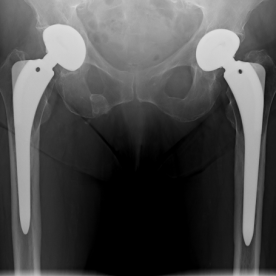

1) Arthrose

Bei einer Arthrose handelt es sich um eine Knorpelabnutzung in einem Gelenk, wobei unterschiedliche Ausprägungsgrade möglich sind. Je nach Ausprägungsart kommen konservative (Entzündungshemmende Medikamente, physikalische Therapie, orthopädische Hilfen) oder operative Verfahren (arthroskopische Spülung bzw. Gelenktoilette, Knochenumstellungen, Knorpelknochenzelltransplantationen oder prothetische Versorgung) in Frage.